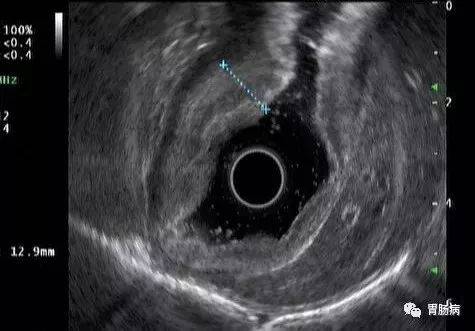

超声提示胃壁黏膜层及黏膜下层明显增厚并融合,层次消失。

在超声内镜评估过程中,其中超声图像显示胃壁第三层超声结构(黏膜下层)可见星点状中断征象,符合革囊胃(也叫皮革胃,浸润性胃癌)的诊断!

内镜超声检查视频,视频中可见胃壁黏膜层及黏膜下层广泛增厚融合,增厚融合的黏膜下层局部呈星点状不连续。